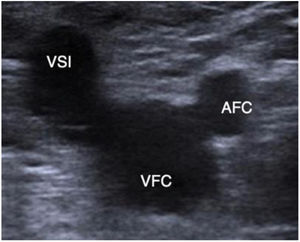

Comenzaremos el estudio al nivel de la unión safenofemoral en modo B (imagen de Mickey Mouse): deberíamos buscar la posible causa del reflujo, que en la mayoría de los casos estará causado por incompetencia al nivel de la unión safenofemoral (fig. 13).